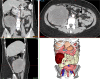

This case report presents the surgical management of a complex abdominal sarcoma in a 33-year-old female patient, emphasizing the pivotal role of advanced imaging and three-dimensional (3D) printing technology in optimizing surgical outcomes. The study aimed to explore the clinical value of integrating computed tomography, magnetic resonance imaging, and patient-specific 3D-printed models for preoperative planning, intraoperative navigation, and postoperative evaluation. A multidisciplinary team utilized Mimics23 software to generate a detailed 3D reconstruction of the tumor and its intricate anatomical relationships with the ileocecal region, appendix, and colon. This model guided the precise resection of a 15 × 10 × 10 cm high-grade sarcoma, minimizing damage to adjacent critical structures. The technology-enhanced approach resulted in complete tumor excision with clear margins, and postoperative no complications. This case underscores the potential of 3D visualization and printing to address the challenges of complex abdominal sarcomas, offering a paradigm for personalized surgical strategies in oncology.